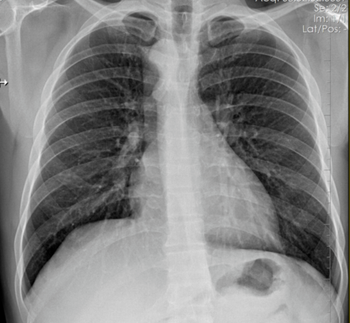

A construction worker presents with a dry cough, can you diagnose this patient?